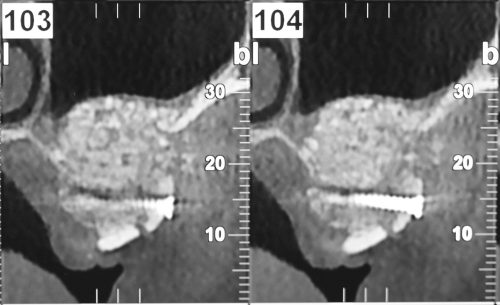

L’intervention chirurgicale consiste en une reconstruction osseuse du maxillaire ou de la mandibule avant la mise en place des implants dentaires par votre chirurgien.